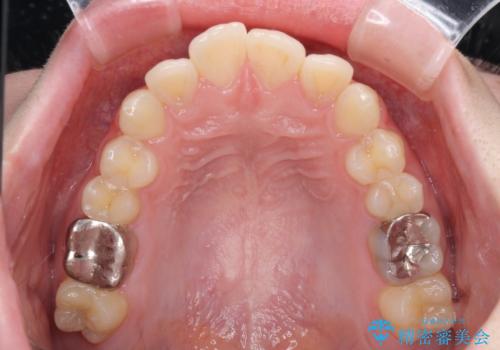

- 上下歯列全体のデコボコを気にして来院された患者様です。

主に下顎歯列全体の後方移動とIPR(歯と歯の間を削る)によってデコボコが解消するように設計し、インビザラインにより治療を行うこととしました。

1年半程度で終了するのではないかと予想しましたが、途中1年以上の来院がなく、トータルで3年の時間がかかってしまいました。

前歯のデコボコはより改善することが望ましい状態でしたが、患者様の希望により終了することとなりました。